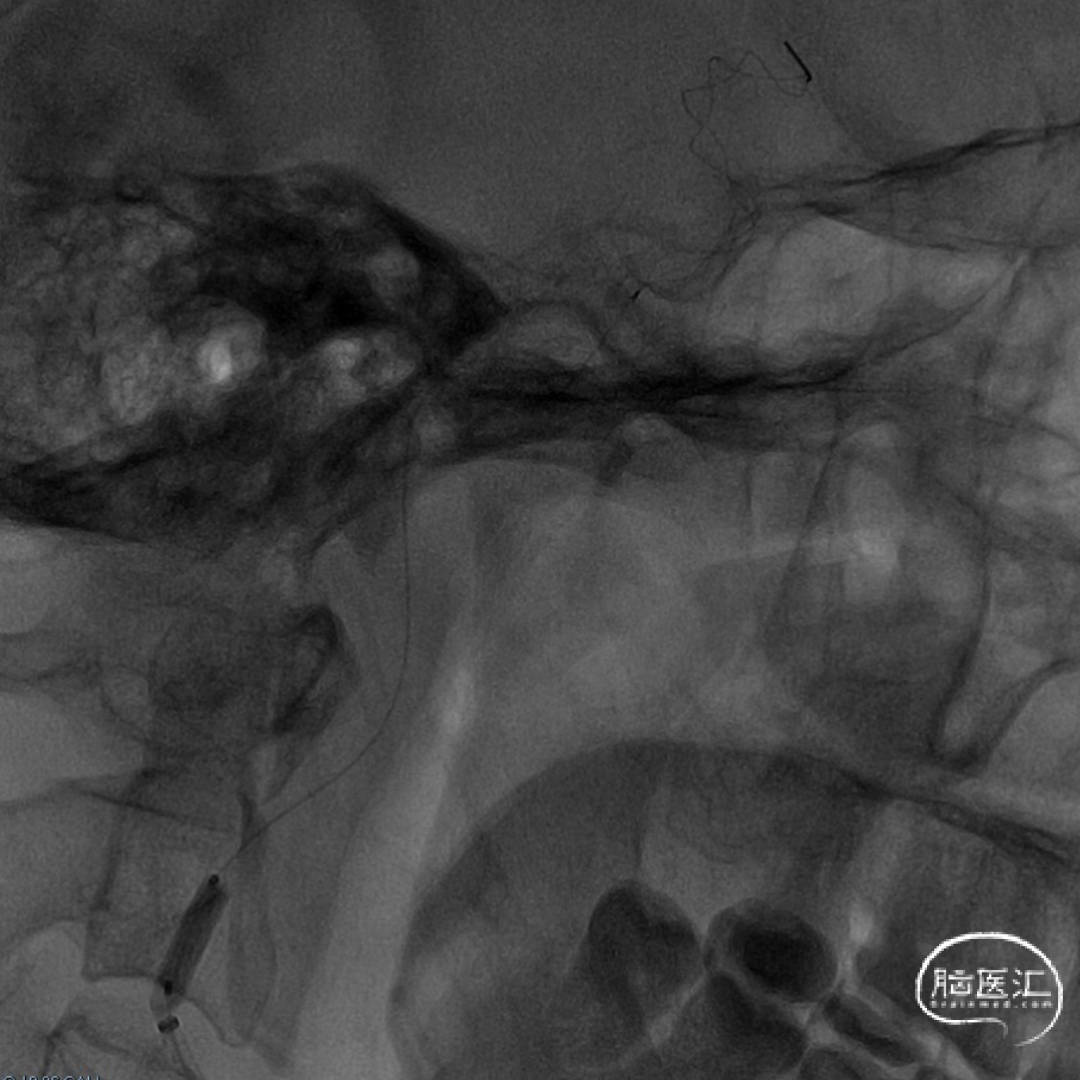

术前DSA造影显示左侧颈内动脉自起始段闭塞,C6眼段以上供血区由颈外动脉眼动脉反向代偿供血,左侧大脑中动脉供血区由前交通动脉代偿供血。

造影后引导下,以0.014in×185cm 微导丝小心通过右侧颈内动脉C1段闭塞处至C3段。随后以0.014in×300cm 微导丝在SL-10微导管支撑下通过闭塞段,成功进入大脑中动脉M1段。

沿微导管送入4.0×30mm Syphonet®取栓支架,于M1-C7段释放作为栓塞保护装置。

沿4.0×30mm Syphonet®取栓支架输送导丝送入3.0×12mm SacSpeed®球囊扩张导管,自C1-C7段分次扩张,每次释压后跟进中间导管至C5段,复查造影显示血流通畅。